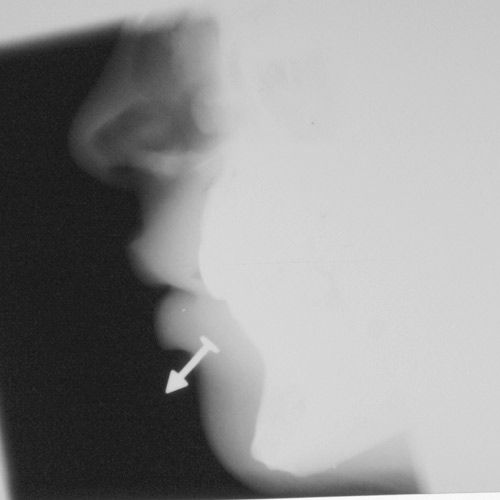

Под рентгеном